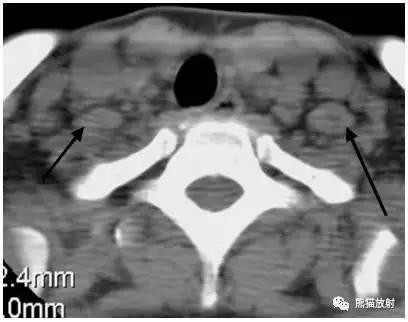

女性,45岁,淋巴瘤。黑箭显示双侧ⅡB区淋巴结。